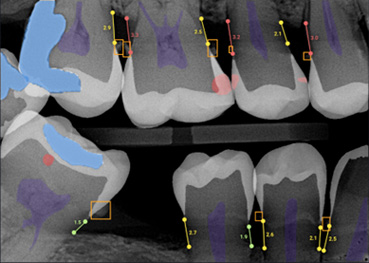

- Figure 3a. Radiographic image

- Figure 3b. Same image with annotations

Source: Overjet, Inc

AI-enabled programs that assist clinicians have existed for some time, such as evaluating the presence and stage of caries lesions based on computerized analysis of radiographs, assisted periodontal charting based on digital data transmission during a periodontal examination, and patient risk assessment programs. Commercially available AI offers more complex assistance with evaluations and diagnoses. Several start-up companies offer AI systems that can assess multiple types of radiographs to identify teeth, restorations, endodontically-treated teeth, implants, and can identify and evaluate dental caries, calculus, periodontal disease, periapical lesions, other pathologies, and anatomical anomalies. (Figure 3a,b) Results from a number of AI systems are supportive of its use in evaluating bitewing, periapical and panoramic radiographs, and in assessing dental caries, and bone loss quantification.16Schwendicke F, Rossi JG, Göstemeyer G et al. Cost-effectiveness of Artificial Intelligence for Proximal Caries Detection. J Dent Res 2021;100(4):369-76. doi: 10.1177/0022034520972335. ,17Baydar O, Różyło-Kalinowska I, Futyma-Gąbka K, Sağlam H. The U-Net Approaches to Evaluation of Dental Bite-Wing Radiographs: An Artificial Intelligence Study. Diagnostics (Basel) 2023;13(3):453. doi: 10.3390/diagnostics13030453.,18Başaran M, Çelik Ö, Bayrakdar IS et al. Diagnostic charting of panoramic radiography using deep-learning artificial intelligence system. Oral Radiol 2022;38(3):363-9. doi: 10.1007/s11282-021-00572-0.,19Overjet. https://www.overjet.ai/dso/ In a recent study, the ability of a single AI system to detect dental caries as well as periapical periodontitis was found to be more accurate than clinical detection alone among young dentists.20Li S, Liu J, Zhou Z et al. Artificial intelligence for caries and periapical periodontitis detection. J Dent 2022;122:104107. doi: 10.1016/j.jdent.2022.104107. Additionally, the overall accuracy for experts increased with the aid of the AI system and reduced inter-observer differences.